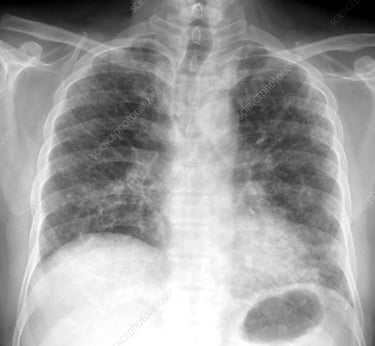

3. İdiyopatik Pulmoner Fibrozis (IPF): "Bilinmeyen"den "Belirlenmiş"e

Dünyada yaklaşık 3 milyon kişinin mücadele ettiği İdiopatik Pulmoner Fibrozis, sıklıkla 50 yaşın üzerinde ve genellikle erkeklerde görülüyor. Tıpta "idiyopatik" terimi, nedenini henüz bulamadığımız durumlar için kullanılan bir itiraftır. Ancak de Dombal tarzı Bayesyen analiz ve fonksiyonel tıp merceğiyle baktığımızda, IPF (idiopatik Pulmoner Fibrozis) bir tesadüf değil, bir "multi-hit" (çoklu darbe) sonucudur.

4. Teşhisin Bayesyen Gücü: Algoritmik Yaklaşım

Tanı koyarken sezgilere değil, olasılıklara dayanmalıyız. Yüksek çözünürlüklü BT (HRCT) ve klinik bulguların tanısal gücü:

HRCT (UIP Pateni) Sens: %90 - 95 Spe: %90 - 98 LR+ 9.5 - 45 LR- 0.05

Not: LR+ değerinin 10'un üzerinde olması, o bulgunun tanıyı neredeyse kesinleştirdiğini gösterir. HRCT’deki tipik UIP (Olağan İnterstisyel Pnömoni) görünümü, Bayesyen analizde "post-test olasılığını" %95’in üzerine çıkarır.